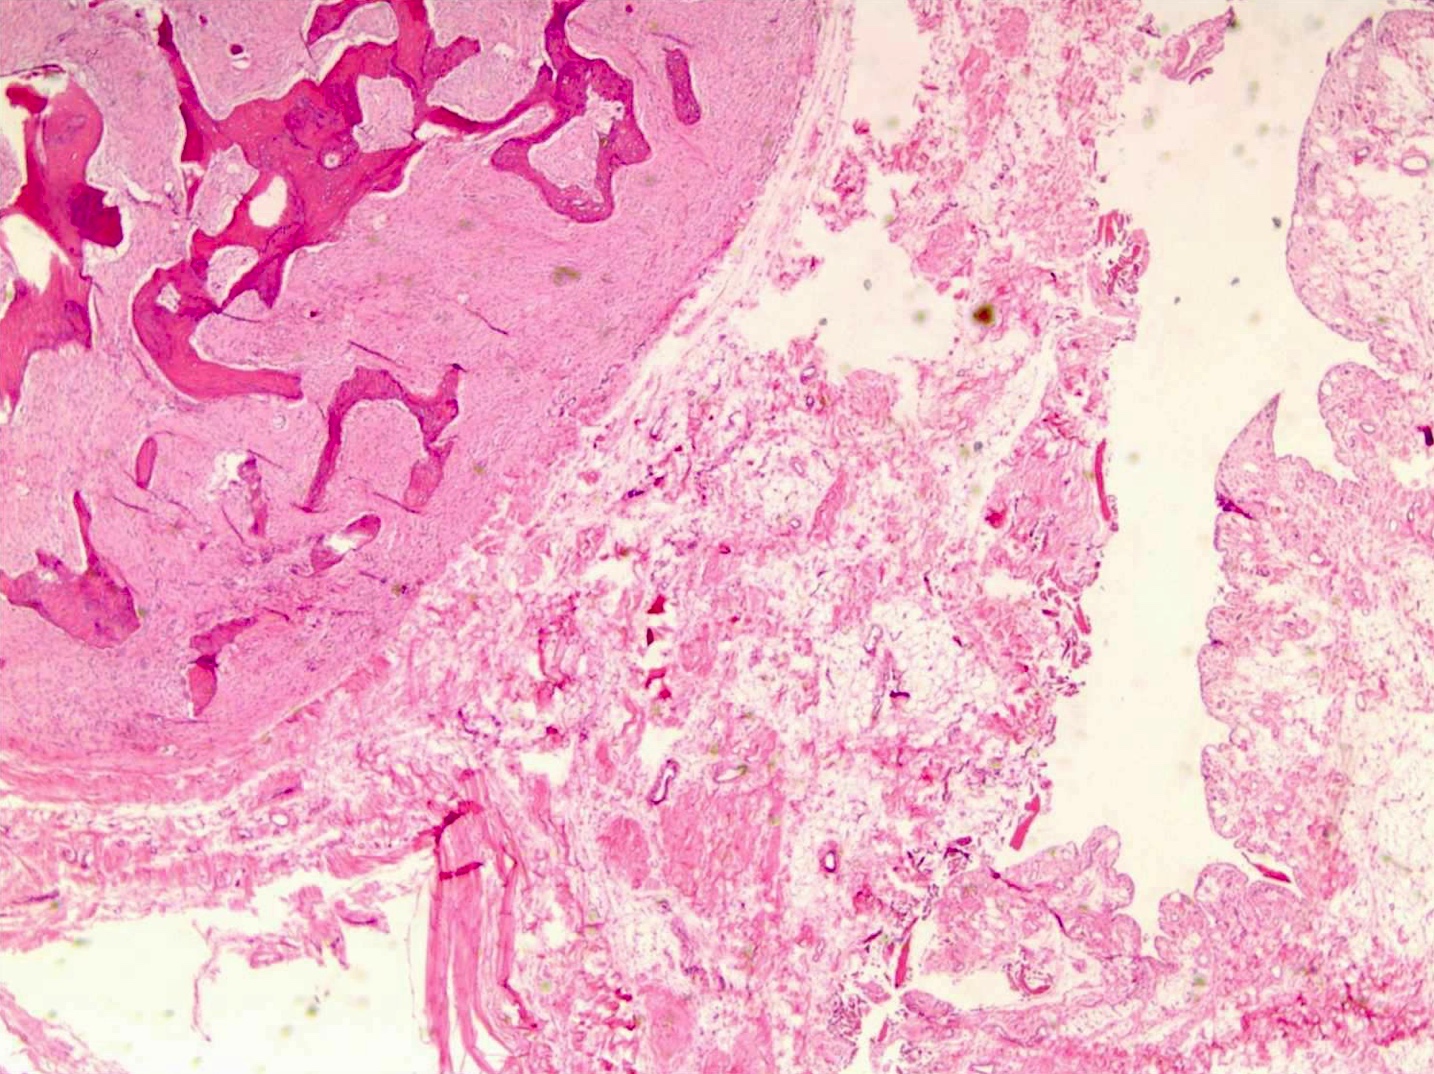

- Parosteal osteosarcoma:

- Invasion: tumor invades soft tissue; 25% invade bone (cortex / medullary)

- Neoplastic cells: fibroblast-like spindle cells (minimal atypia); between bony trabeculae (may be hypocellular)

- Scattered mitoses may be seen

- Neoplastic bone: parallel bony trabeculae (osteoblastic rimming may be present)

- Cartilage (present in ~50% of cases):

- Nodules within lesion (hypercellular)

- Cartilage cap: partially overlays tumor (moderate cellularity, chondrocytes are not arranged in columns, mild to moderate atypia)

- Dedifferentiation (15 - 25% of cases): abrupt transition to high grade sarcoma

Microscopic (histologic) images

Contributed by Jesse Hart, D.O., Borislav A. Alexiev, M.D. and AFIP